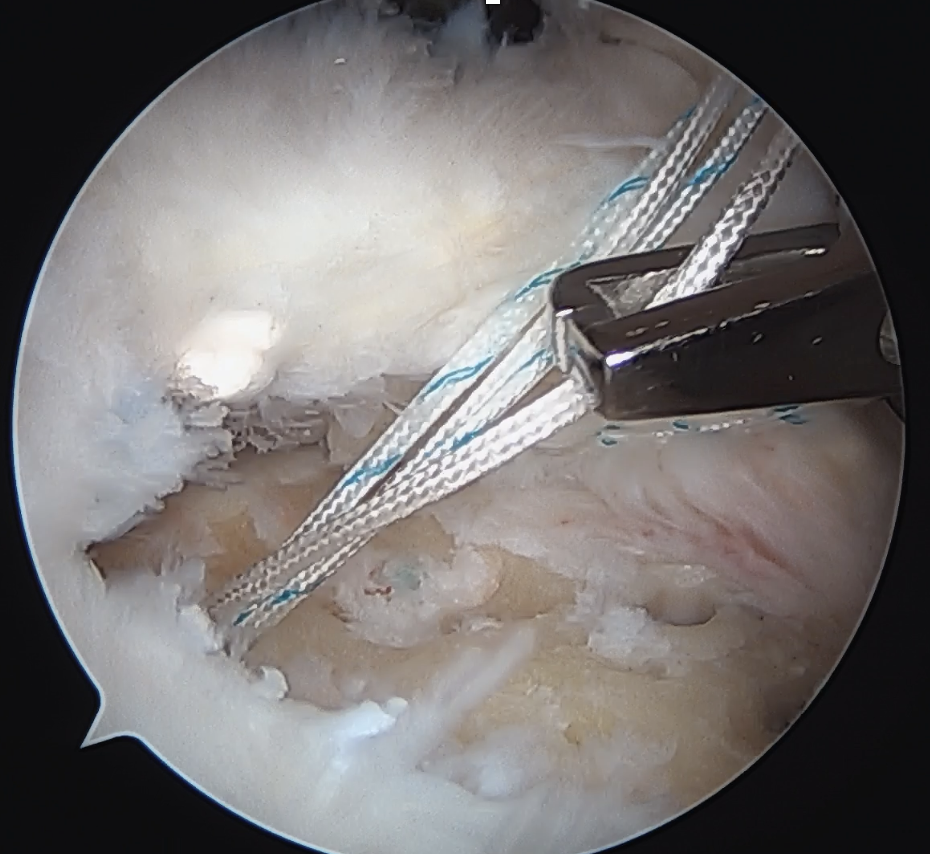

Trans-osseous equivalent / suture bridge

- cross sutures from medial row to lateral row

- increase contact between cuff and footprint

Double row / suture bridge

- use medial row sutures

- secure in knotless lateral row anchors

repairrepairrepair